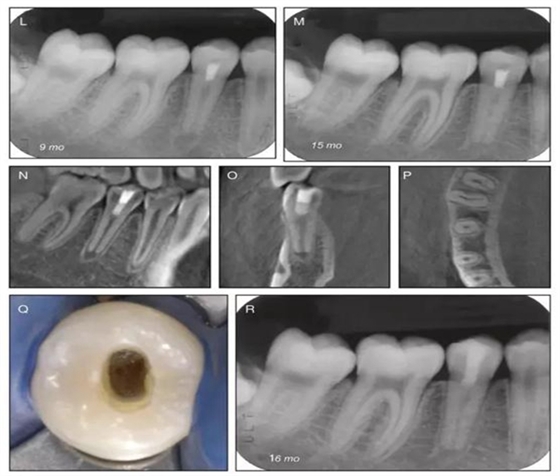

原則上年輕恒牙的牙髓治療應(yīng)盡可能以保存活髓的方式以便不影響牙根繼續(xù)發(fā)育。本文3個病例均描述了根尖尚未發(fā)育完成的下頜前磨牙被確診為牙髓壞死伴有大面積根尖病損,治療過程中在根管內(nèi)發(fā)現(xiàn)了部分活髓,而采用活髓切斷后都取得了很好的療效。